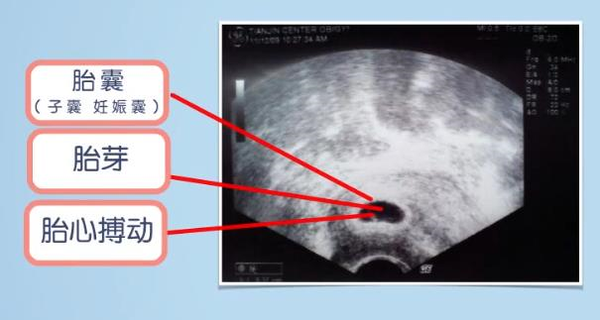

胎囊 胎芽 胎心到底是什么 育儿 品阅网

胎芽是什么样子 胎芽胎心是什么 豪友网

孕囊 胎芽 胎心代表什麼 捉摸不定的胎心胎芽 什麼時候出現 壹讀

孕早期孕囊 胚芽 胎心完美三部曲 每日頭條

孕6周胎芽發育簡報 B超單上寫有這 四物 表明 坐胎 穩定 每日頭條